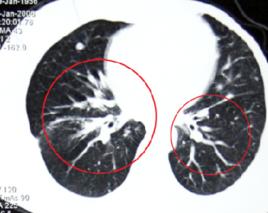

(3)呂廣種方法是斷層攝影。把身體的某一部份隔成一定區隔,進行調光斷層診斷法。例如:針對肺結核進行斷層攝影,分1公分或0.5公分厚度,對肺作斷層攝影。

(4)CT(com puter tomography)診斷:這種方法對腦部、肝臟、胰臟等等的診斷使用較多。